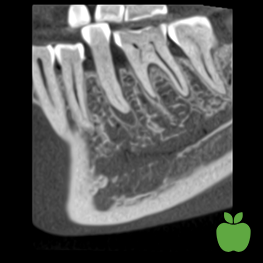

高解像度と標準線量は必ずしも必要ではなく、多くの場合はそれ以下で十分です。例えば、インプラント計画や親知らず抜歯のために下顎神経系を観察するには、プランメカ Ultra Low Dose画像で十分で、極めて低い線量で撮影できます。

超低線量によるHD解像度 ボクセルサイズ150 μm、患者線量〜32 μSv

超低線量による標準解像度 ボクセルサイズ200 μm、患者線量〜20 μSv

超低線量による低線量解像度 ボクセルサイズ400 μm、患者線量〜6 μSv